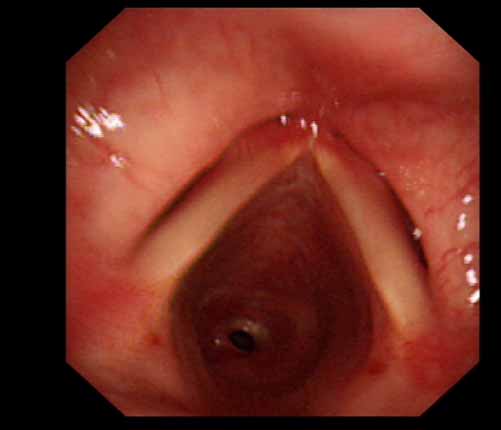

患者李某某,女,45歲,因氣管插管咳嗽、喘憋10天入院。頸部CT檢查示聲門(mén)下約20mm處氣管明顯狹窄,狹窄段長(zhǎng)約26mm,最窄處直徑約4.4mm。支氣管鏡檢查見(jiàn)聲門(mén)下約2cm氣管呈漏斗狀縮窄,直徑約4-5mm,支氣管鏡無(wú)法通過(guò)。經(jīng)科室討論,決定行電子支氣管鏡下氣管球囊擴(kuò)張治療。與患者及家屬充分溝通并經(jīng)三方見(jiàn)證談話簽署知情同意書(shū)后,在患者持續(xù)吸氧、局麻下,科主任于世倫主任醫(yī)師帶領(lǐng)治療小組為患者實(shí)行電子支氣管鏡下氣管球囊擴(kuò)張術(shù)。手術(shù)過(guò)程順利,出血量很少,術(shù)后患者呼吸困難癥狀即可明顯緩解。10天后行二次擴(kuò)張,患者日?;顒?dòng)無(wú)明顯喘憋,二次術(shù)后5天出院。

術(shù)前聲門(mén)下的漏斗樣狹窄口 術(shù)中球囊擴(kuò)張 術(shù)后擴(kuò)張開(kāi)的氣管管腔